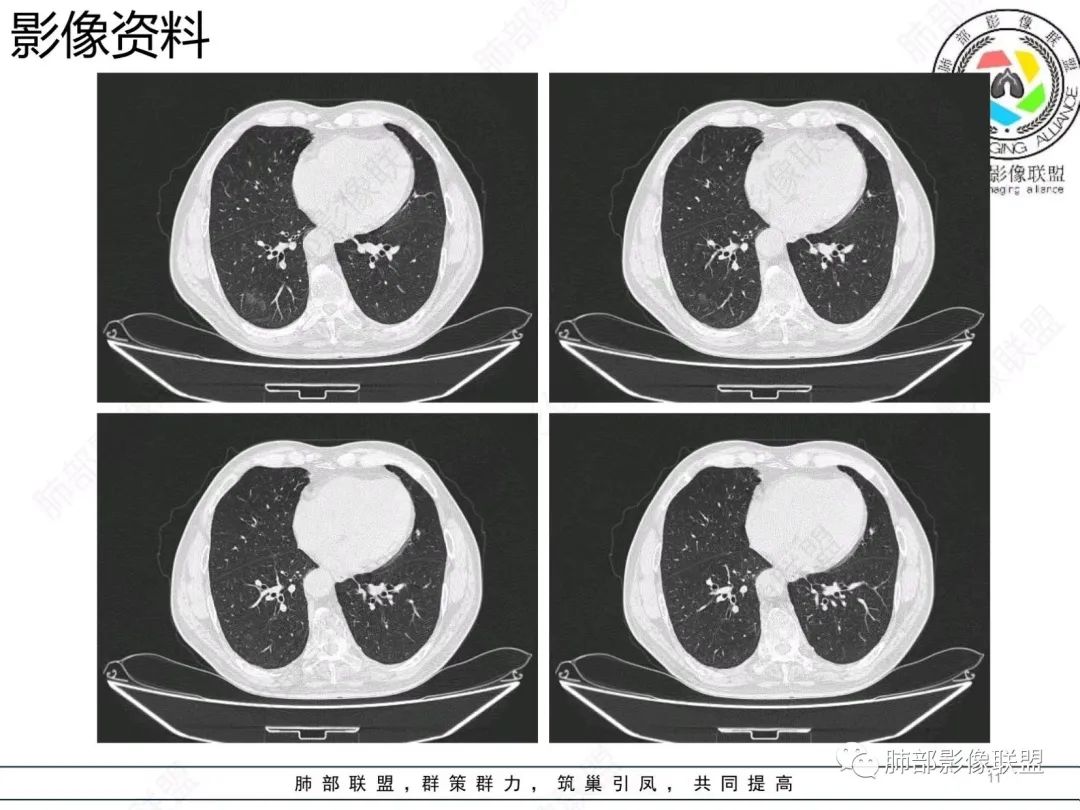

结节型粘液腺癌,具有血管弯,支气管截断,磨玻璃边界清楚等恶性征象,同时磨玻璃内部较糊,似清非清,不符合普通腺癌附壁生长特点,更像局限的粘液成分。收缩力不强,胸膜局部微积液,内部小空洞(考虑局部粘液排除形成),所以考虑结节型粘液腺癌。

这个结节型粘液腺癌还是比较典型的

区别1:结节期(影像说结节型)粘液腺癌,粘液成分还大多数局限于粘液腺癌细胞的胞浆中,没有飘出去,所以粘液密度不明显,周围的磨玻璃成分大多数还是分散于肺泡壁上的粘液腺癌细胞,所以边界相对较清楚(时间越晚,飘出去的粘液越多,边界就会越不清楚了),因为胞浆中的粘液成分显得较糊,有点似清非清。而普通腺癌附壁生长的腺癌细胞胞浆中没有粘液,所以非常清楚。

区别2:粘液腺癌的MGGN收缩力不强,普通腺癌的MGGN收缩力明显。

粘液腺癌CT表现:

1.结节型肺粘液腺癌以中老年女性多见,单发,发病部位常位于两下肺胸膜下(肺外周带)。

2.多数病灶具备典型恶性肿瘤征象,但是不典型者仍不少见。可有分叶和棘状突起,但较少出现典型毛刺征。强化程度不如一般的腺癌病灶那么显著。

3.病灶常呈圆形或不规则形,实性结节略多于混合磨玻璃结节,少见于纯磨玻璃结节;或囊实性结节影或肿块,密度混杂,部分可出现钙化;病灶边界可清楚,也可模糊,须与炎性结节鉴别;周围可有类圆形磨玻璃密度卫星灶;表现为实性结节病灶,收缩力可能表现不明显,较少胸膜凹陷或血管集聚,须与良性结节鉴别。

4.原发性肺粘液腺癌侵袭力相对较低,发展慢;病灶较少破坏支气管及血管,可表现为血管造影征及空气支气管征。较少胸膜侵犯,也较少肺门纵隔淋巴结转移。

病理影像:

1.病理基础:肺原发性粘液腺癌的肿瘤细胞产生大量粘液,聚集于细胞内,破入细胞间隙甚至肺泡、末梢细支气管,致使病灶密度增高呈混合磨玻璃或实性结节。

2.粘液的直接扩散和漂移,致使病灶边界模糊和病灶呈多灶性生长。

3.粘液的重力效应致使病灶常位于胸膜下或叶间胸膜附近。

4.病灶内气管、血管破坏不明显,可出现血管造影征及空气支气管征;也提示病灶侵袭力较低。

5.粘液的张力(占位效应)常可抵消病灶收缩力,致使病灶收缩力表现常较弱。